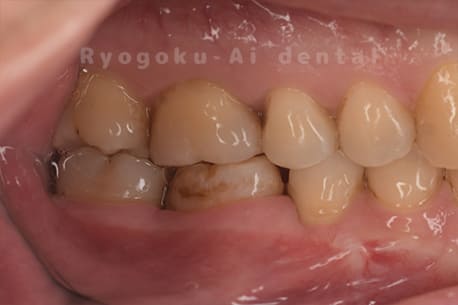

他院で右下の根の治療を行い、セラミックを被せる説明をされていたが、根の治療が終わらないため転院された患者さんです。隣の親知らずの抜歯の必要性と、根の治療を行なっている歯牙の予後が悪いため、移植治療を提案し、右下の親知らずの抜歯と同時に、右下の奥歯(7番)への移植治療を行いました。被せ物を行う必要もなく、順調に経過してます。